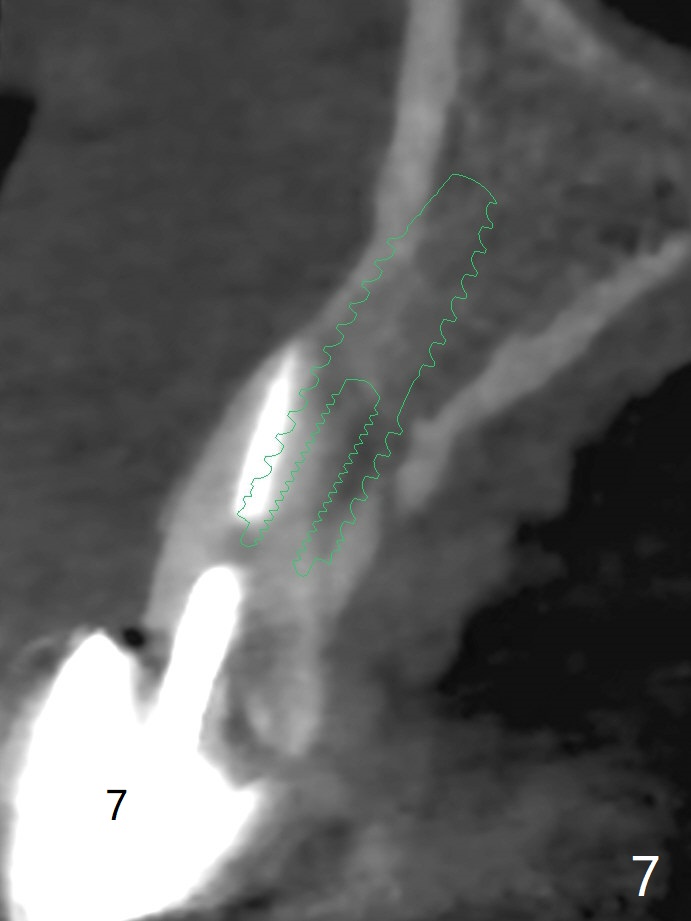

A 34-year-old woman requests fixing the failed anterior FPD (Fig.1). The edentulous alveolus looks thin; 1-piece implant may be indicated at most. A regular narrow 2-piece implant will be placed at the lateral incisor (Fig.2). CT is necessary for treatment planning. Impression has been taken for stent fabrication. 34岁女,一年半前来诊所(图一,二(侧切牙种植,做悬臂桥,暂时保留左上1牙冠)),希望修复右上门牙桥。现在终于要求立即做,基牙处牙龈红肿 (图三(今天做深洗)),牙桥颊侧移位(图四),侧切牙(7号牙)牙槽嵴也不是很宽,植入3.5毫米植体(两段式, IBS)还勉强(图五)。为了简化,避免悬臂桥,我还想在中切牙(8号牙)无牙处植入一段式2.5毫米植体(图六),适当做些牙槽嵴劈开(图六右上图:红线; from IBS cassette)。这周末徒手植入,她离开时应该有固定临时修复物。

一段式植体似乎不美观,其实它适用于近中远中空间狭窄地方,如这个病例,而两段式植体显得太粗,没有空间形成牙龈乳头,况且容易以后导致植牙周围炎。即刻临时牙冠手术第一天就起到美观作用,术后三四个月中反复调整,为永久性牙冠奠定基础。以下手术步骤就是为了这个目的。在中切牙之间切断牙桥,为右上1狭窄牙槽嵴拍摄照片(颊侧,咬合面观),切口,铬羊肠缝线牵拉,外科车针去除尖端牙槽嵴直到后者宽度达到~ 3毫米,使用1.2毫米一段式钻头,8 毫米,插入一个已经折断同样大小车针作为定位;拔除侧切牙,拍摄各式各样刮匙和肉芽组织去除器械,用1.6毫米钻头在腭侧骨板钻洞,深度9毫米,拍摄术中第一张根尖片;在中切牙处使用片状骨凿稍做骨扩张,必要时旋转式扩大器,之后完成牙槽嵴下植体放置,侧切牙牙槽窝以及中切牙术野插入无絮棉布,做必要基台制备,使用成品临时牙冠制作两个分开牙冠,确保牙龈下边缘,取出棉布,植骨,放置PRF膜,插入临时牙冠,尤其是中切牙牙冠和骨粉将改善颊侧,腭侧(与图四箭头对比)饱满度,最后缝合,调整咬合。7,8号牙骨质密度分别为700和 500单位(图七,八)。